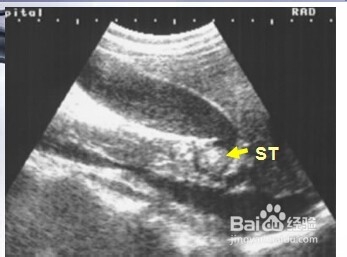

3、三:胆囊颈部结石。